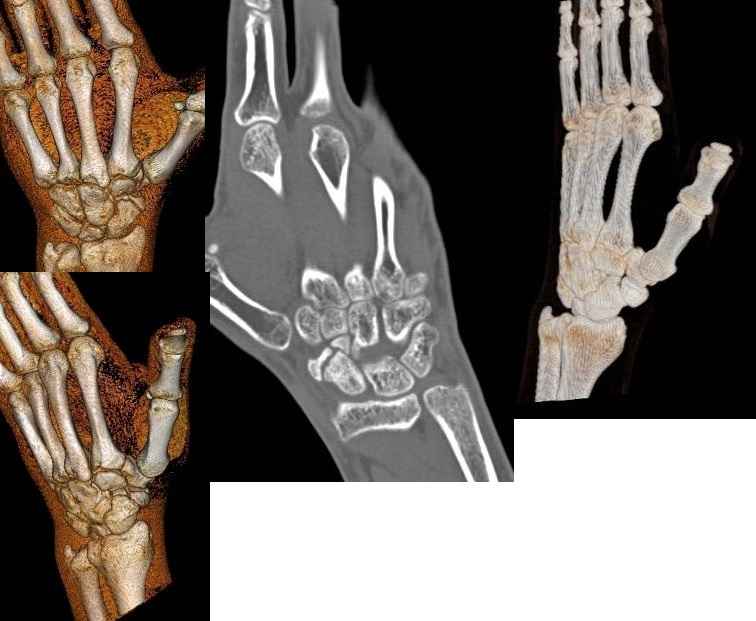

[Ortho] Несвежий перелом ладьи

Извините, снимки обнаружились :)